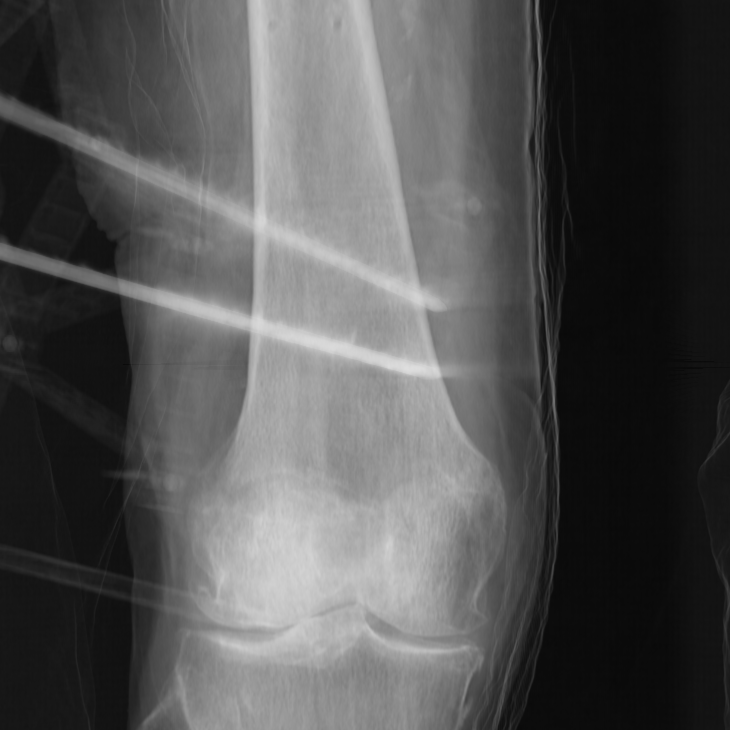

Segmenting the femur CT model into these three substructures can be performed preoperatively. However, segmenting contour pixels for each substructure intraoperatively in the X-ray images presents several challenges. The first challenge is the need for speed, as this process must be completed quickly to integrate seamlessly into standard surgical workflows. Additional challenges arise from the nature of medical imaging and the characteristics of X-ray images, such as low contrast, noise, overlapping structures, unclear or ambiguous boundaries, and artifacts. For reference, see Figure 17.

Five cadaveric distal femur specimens (three female, two male) were obtained from a certified anatomical donation program with ethical approval. Four specimens were right-sided, and one was left-sided, with a BMI range of 19–28. Additional details are provided in Online Resource 1. The CT data were acquired using the Siemens CT NAEOTOM Alpha with a resolution of 512512px and a slice thickness of 0.2mm. The X-ray images were acquired using a Siemens XA - Fluorospot Compact S1 with a resolution of 976976px and a sensor size of 296.7296.7mm. During image acquisition, the specimens were placed on a radiolucent table, while the fiducial remained fixed relative to the bone throughout X-ray imaging. The images were taken from 10 perspectives per specimen, with the C-arm rotated around the specimen at approximately 9-degree intervals. X-ray image poses were estimated using our fiducial marker.